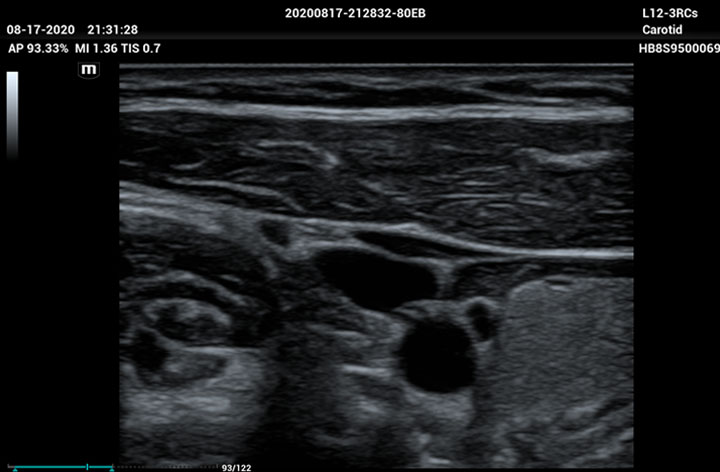

The ME8 Ultrasound System has been thoughtfully designed to overcome the obstacles clinicians face in today’s challenging healthcare environment. Powered by our groundbreaking software-based beamformer technology, ZONE Sonography® Technology+(ZST+), the ME8 Ultrasound System empowers decision-making by providing end-users best-in-class image quality and access to a comprehensive suite of workflow enhancement tools.

Advanced Technologies

Enhancing Clinical Confidence